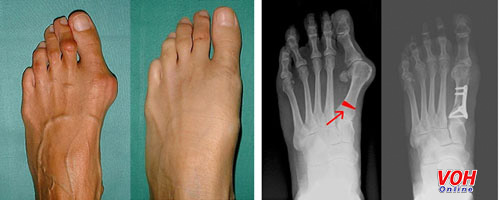

Tình trạng ngón cái vẹo vào trong sẽ làm cho bàn chân đau đớn do lực ma sát gây ra trong quá trình đi lại.

Chứng bệnh này liên quan đến quá trình đi giày cao gót thường xuyên và một số trường hợp do yếu tố di truyền. Đã có nhiều bệnh nhân nhờ đến bác sĩ phẫu thuật chỉnh hình để cải thiện về nguyên dạng ngón chân.

Tuy nhiên, nếu sau quá trình phẫu thuật vẫn tiếp tục đi giày cao gót thì tất yếu sẽ dẫn đến tật vẹo ngoài ngón cái cấp độ 2./.